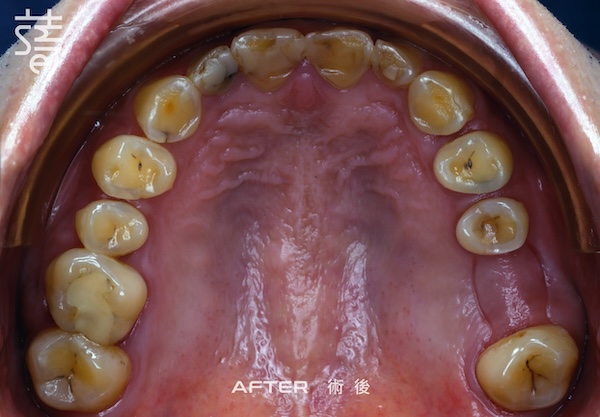

第三階段:全口美學重建 Stage Three: Full-Mouth Aesthetic Restoration

最後進行全口假牙與美學修復。許多人以為這一步只是追求美觀,其實這正是確保牙齒能長期穩定的關鍵步驟,讓美觀與功能同時回歸理想。

Finally, full-mouth prosthetics and aesthetic restoration were completed. Many assume this step is purely cosmetic, but it’s actually crucial for long-term stability.

經過一段完整而細緻的治療,李先生終於重新露出久違的笑容,自然、上鏡,也能自在享受每一口美食。

After a thorough and meticulous treatment, Mr. Li finally revealed a long-lost smile—natural, camera-ready, and able to enjoy every bite with ease.

從矯正、植牙、臨時假牙的調整,到最終假牙的完成,每一步都凝聚著薛醫師的專注與團隊的細心。透過 Modjaw 的動態咬合紀錄與國際專家的臨床經驗,蒔美讓李先生的笑容不只漂亮,更兼具穩定與健康。

From alignment, implants, and temporary prosthetic adjustments to the final restoration, every step reflected Dr. Xue’s focus and the team’s care. With Modjaw’s dynamic bite records and international expertise, Smile ensured Mr. Li’s smile was not only beautiful but stable and healthy.